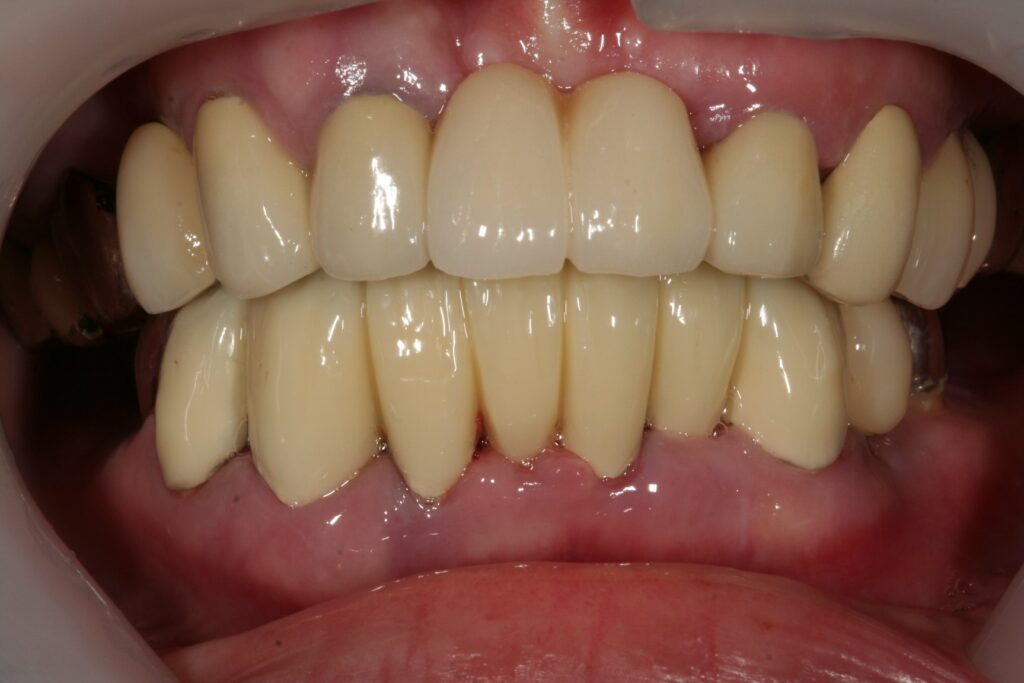

審美歯科 小城 2022.04.19 症例紹介 50代男性歯並びが悪くて食事がしにくいとずっと悩んでおられました。被せモノをして改善していきました。治療回数は2回でした。 症例紹介 久しぶりの更新です。前の記事 小城市倫理法人会次の記事